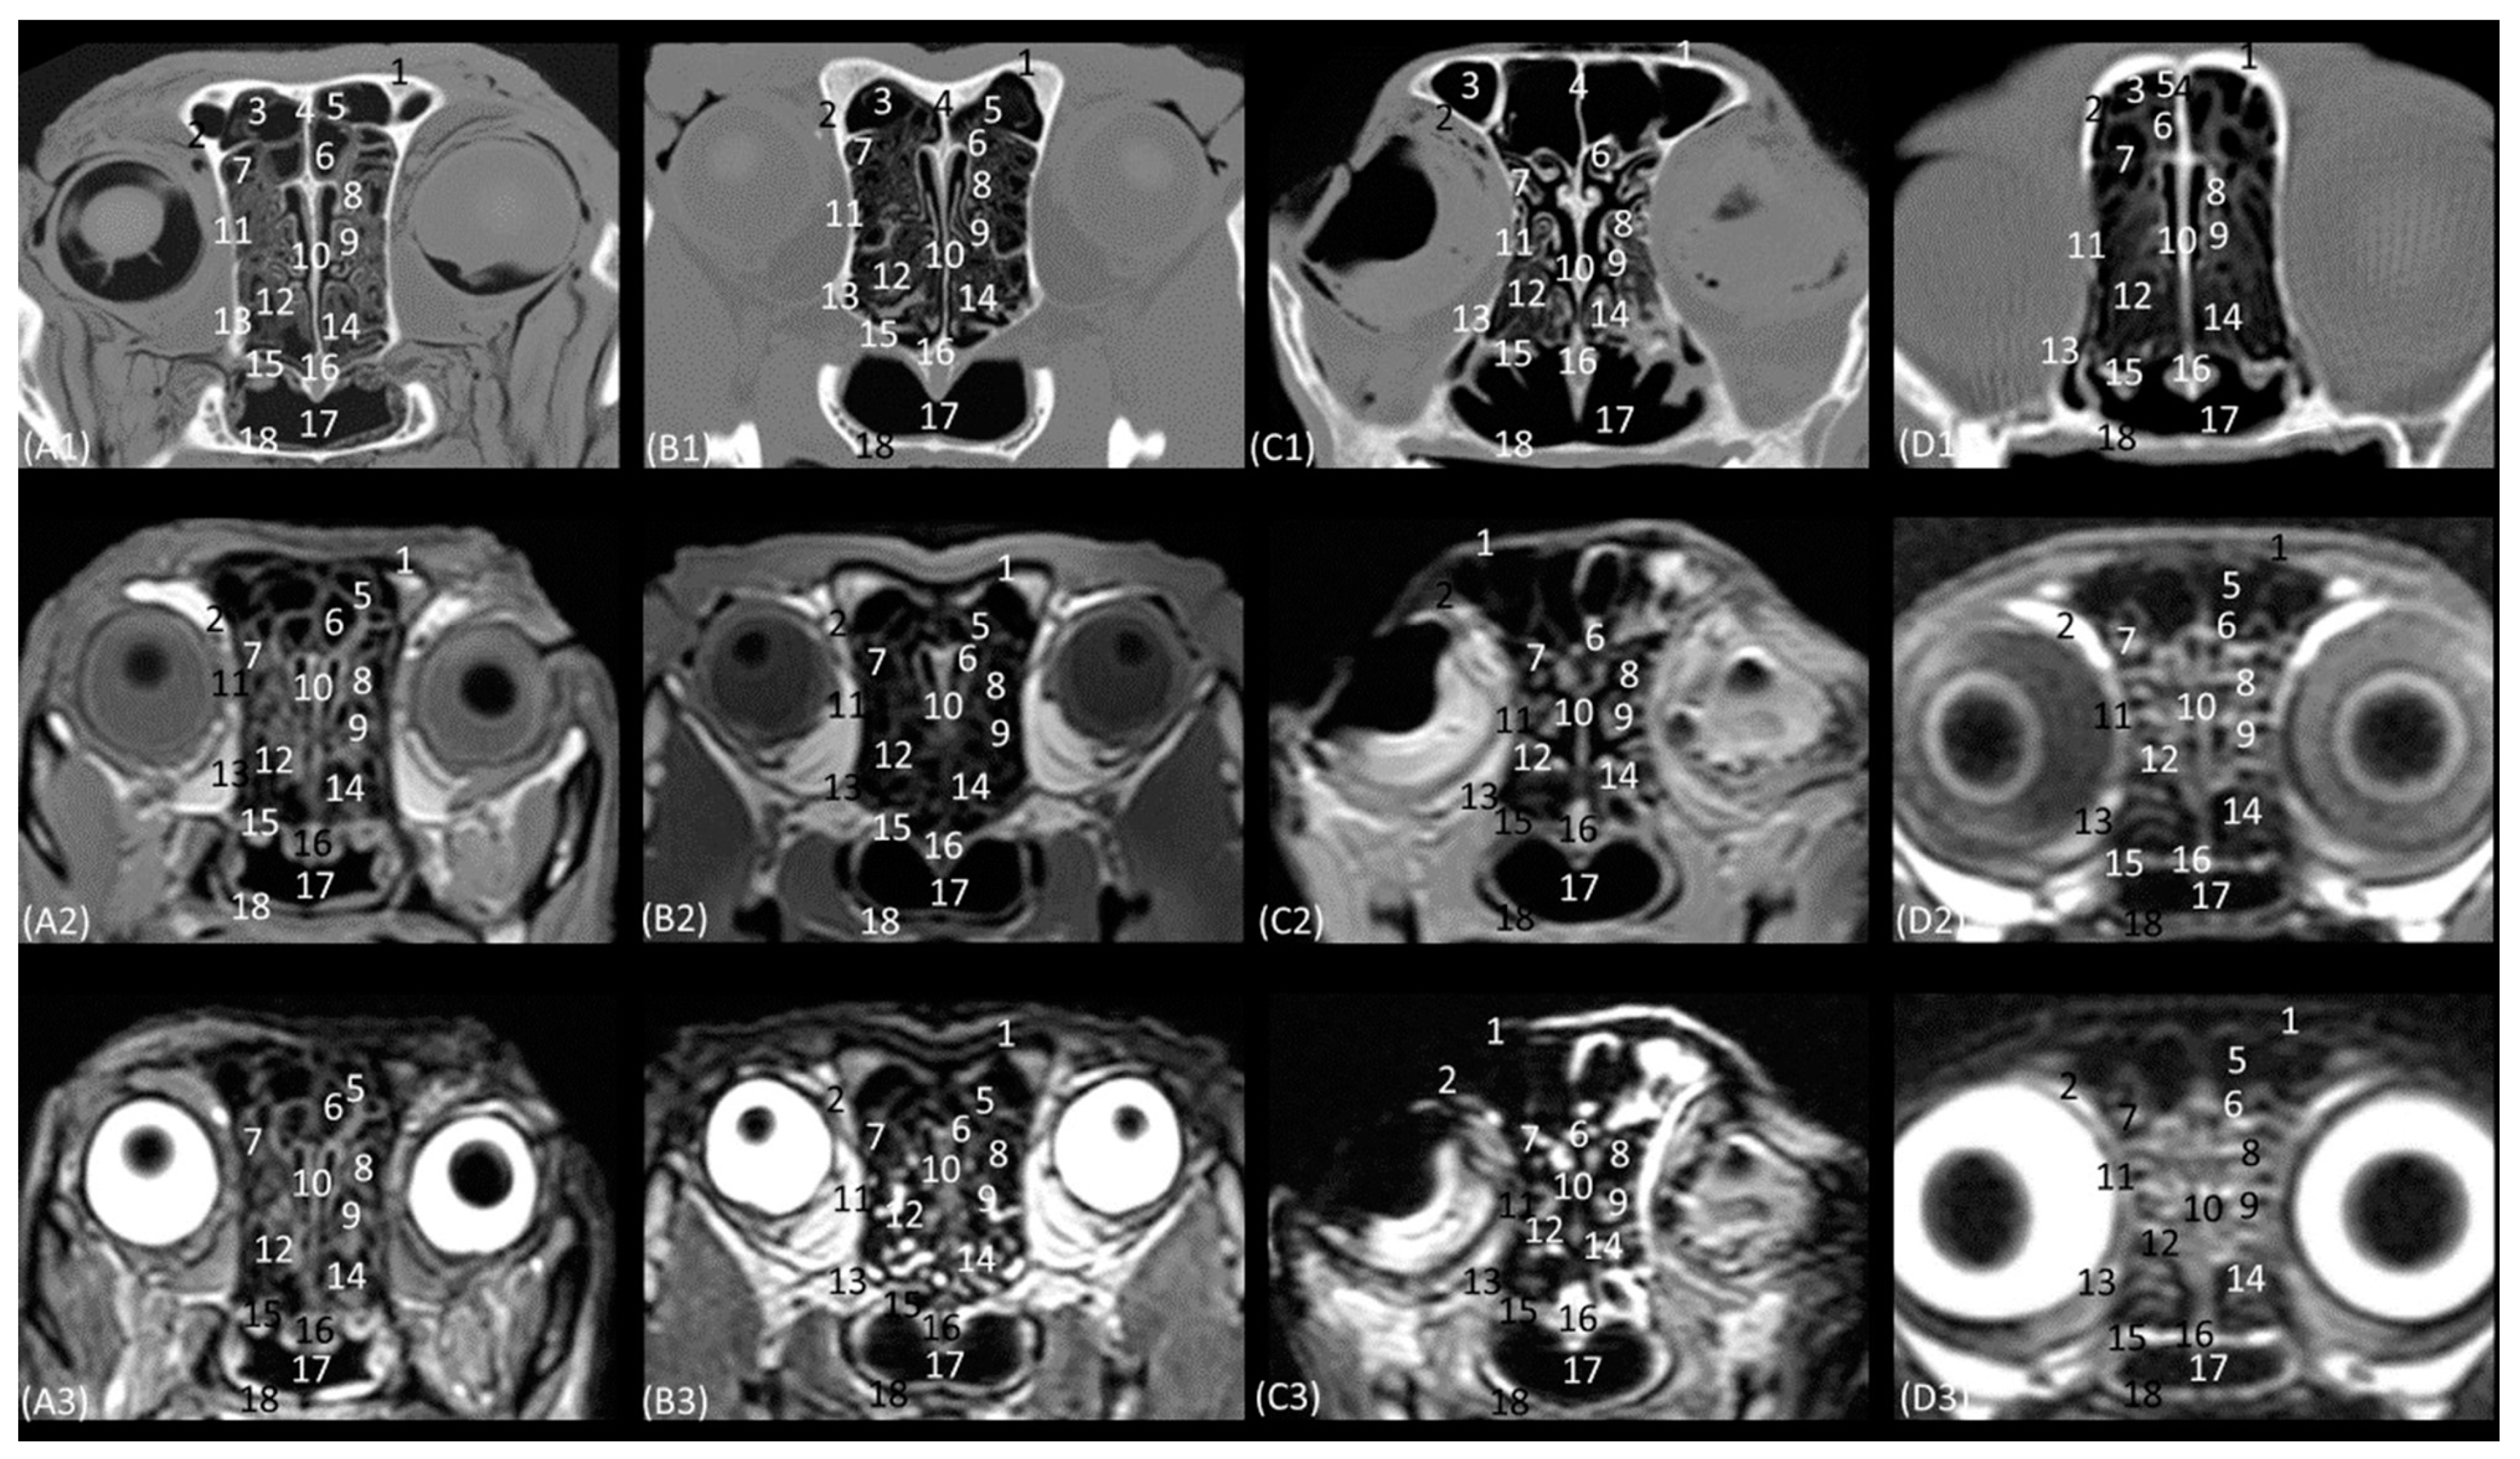

Figure 15 delves into the respiratory portion of the nasal cavity. Three views were observed in the four species, from dorsal to ventral. In the most dorsal view (Figure 15(A1–D1)), the development of the dorsal nasal concha can be seen, starting from the lateral side of the nasal cavity. Ventral to it, the ventral nasal concha was observed, but between the two conchae, the third endoturbinate was also seen. The meatuses can also be observed between the conchae. The dorsal nasal meatus was visualized between the roof of the nasal cavity and the dorsal nasal concha. The middle nasal meatus was located between the dorsal nasal concha and the ventral nasal concha, while the ventral nasal meatus appeared between the ventral nasal concha and the floor of the nasal cavity. Finally, the common nasal meatus was identified between the medial surface of the nasal conchae and the nasal septum. These meatuses were described as narrower in the domestic cat than in the rest of the studied felids. Furthermore, it is worth highlighting how in the cheetah and the lion, the third endoturbinate presents a more sinuous, narrow, and flattened morphology than in the other species. In a more ventral view, the development of the maxillary recess was observed, located laterally to the ventral nasal concha (Figure 15(A1–D1)).

Figure 15. Endoscopic images of the nasal cavity at the level of the dorsal and ventral nasal conchae. The levels of this endoscopic study are shown on the left in the sagittal anatomical sections. Images are observed so that the right side of the head is to the left of the image. (A1A3): Leopard; (B1B3): lion; (C1C3): cheetah; and (D1D3): cat. 1. Dorsal nasal concha; 2. ventral nasal concha; 3. 3th endoturbinate; 4. nasal septum; 5. nasal cavity: roof; 6. dorsal nasal meatus: 7. middle nasal meatus; 8. common nasal meatus; 9. nasal cavity: lateral wall; 10. maxillary recess; 11. ventral nasal meatus; 12. nasal cavity: floor; 13. straight fold; 14. alar fold; 15. basal fold; 16. dorsal part of maxillary recess; 17. ventral part of maxillary recess; 18. beginning of ventral nasal concha in the conchal crest of the maxillary bone.